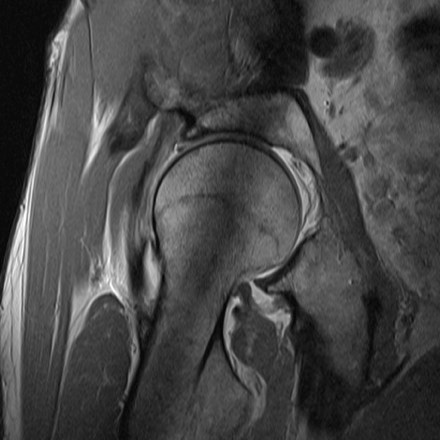

The image seen in Interactive 2.2 shows a typical pincer impingement case. There are already cysts on the acetabular rim, which jut forward and jam against the neck of the femur, particularly during hip bending movements. The animated graphic demonstrates well how impingement (jamming) damages the labrum and, consequently, the articular cartilage.

The neck of the femur impinges on the labrum, initially causing a tear. Over time, the cartilage is also damaged.